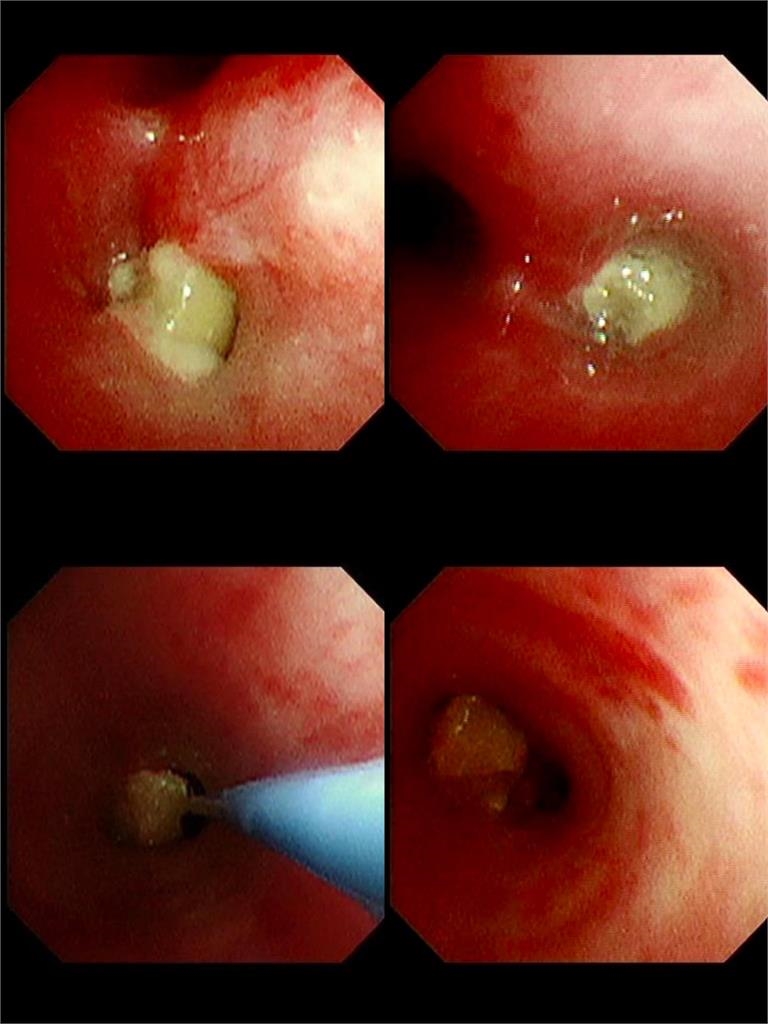

基隆長庚醫院兒科教授級主治醫師廖穗綾今(12日)在臉書粉專發文指出,上週原本要和家人去吃大餐,卻臨時接到一名緊急轉送來的1歲多病童,了解事發經過後,孩子3、4天前阿嬤餵食孫子一整顆花生,接著便開始出現咳嗽與喘鳴聲,雖然剛開始症狀不明顯,但隔天追蹤X光後發現孩童的「肺部已經開始塌陷」,直呼不能輕忽。廖醫師的丈夫賴醫師緊急召集加護病房團隊與資深技術員,準備進行手術。然而手術過程異常艱難,廖穗綾描述,那顆花生已經卡了3天,周圍長出了肉芽,「整顆又大又肥,死死塞住支氣管」,賴醫師表示從來沒有遇到這麼困難的案例,經過長達2個小時的搶救,才把那顆「會跳舞的花生」成功網住、夾出。